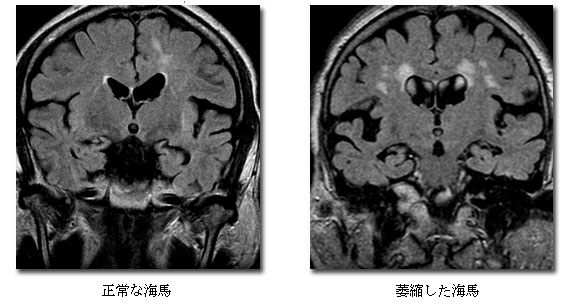

主に脳の形状を調べる検査です。認知症においては記憶をつかさどる海馬と呼ばれる部分が萎縮することがあります。